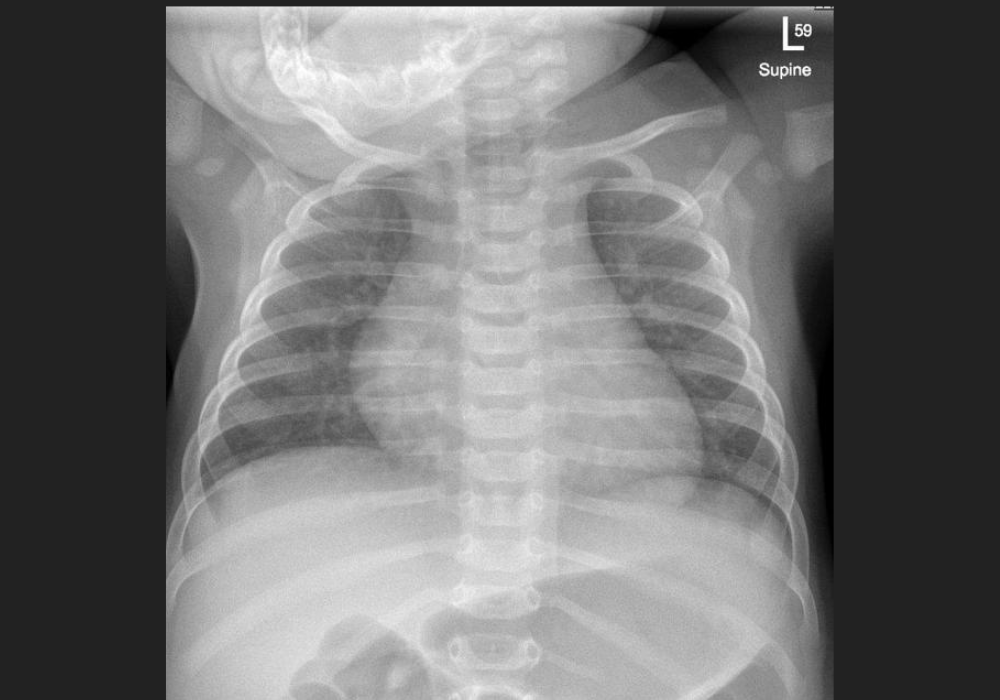

Radiology reading rooms are intentionally dim to optimise image contrast and reduce glare, supporting accurate interpretation. However, prolonged time in such settings coincides with reduce